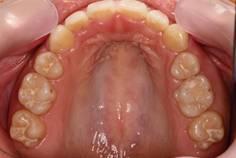

インビザラインによる矯正症例2 22歳女性

治療開始時。正中離開と過蓋咬合がありました

治療途中 5か月後

治療終了 治療開始後7か月